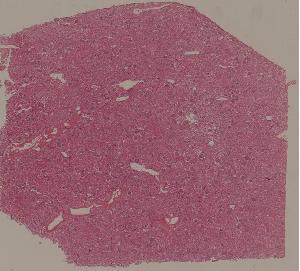

72. Lupus nephritis

低倍视野